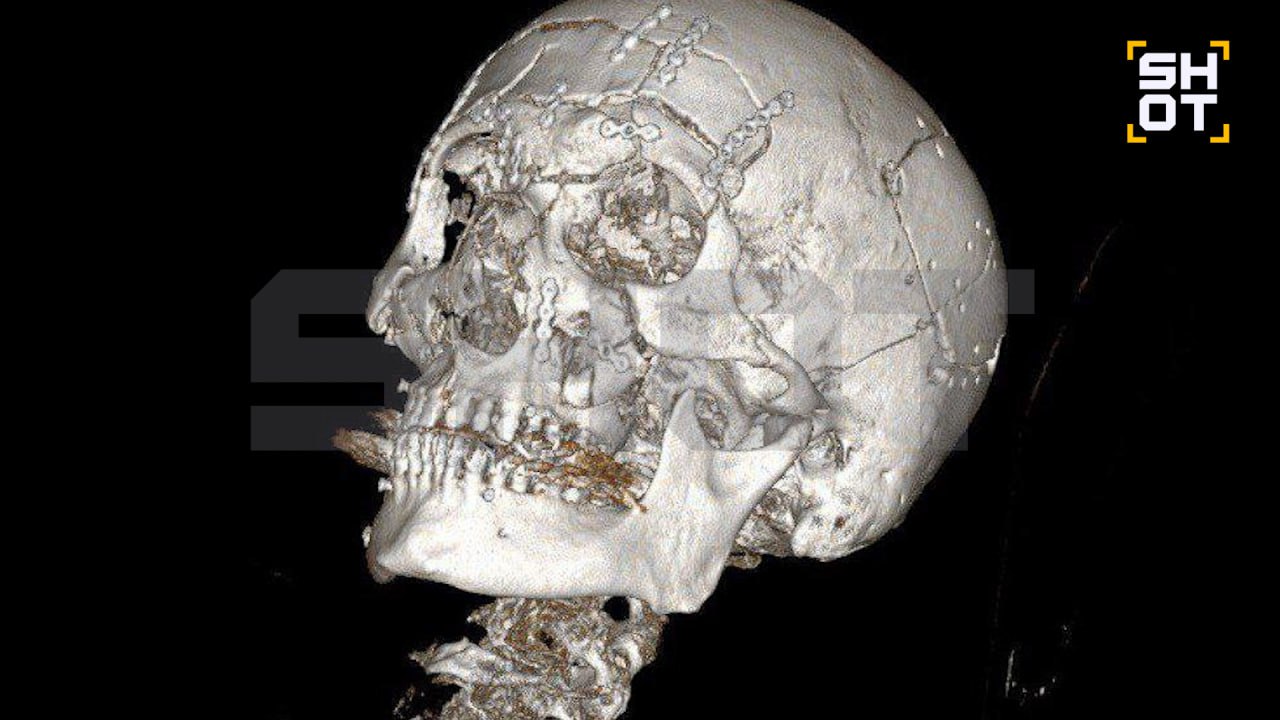

В подмосковном Жуковском произошёл тяжёлый несчастный случай, в результате которого 44-летний мужчина получил множественные травмы лица. По информации источника, он упал со снегохода, что привело к серьёзным повреждениям лобной кости, носовых пазух и челюсти.

Для спасения жизни пострадавшего в Жуковской больнице была проведена сложная операция, которая длилась семь часов. В ходе вмешательства нейрохирурги удалили обломки лобной кости, а также заднюю стенку пазухи и слизистую оболочку. Просвет пазухи был заполнен аутокостной крошкой.

Челюстно-лицевые хирурги восстановили повреждённые участки черепа, включая лоб, глазницы и обе челюсти. Для фиксации использовались титановые мини-пластины. После операции мужчина прошёл первичную реабилитацию и был выписан из больницы. Однако его ждёт длительный период восстановления.